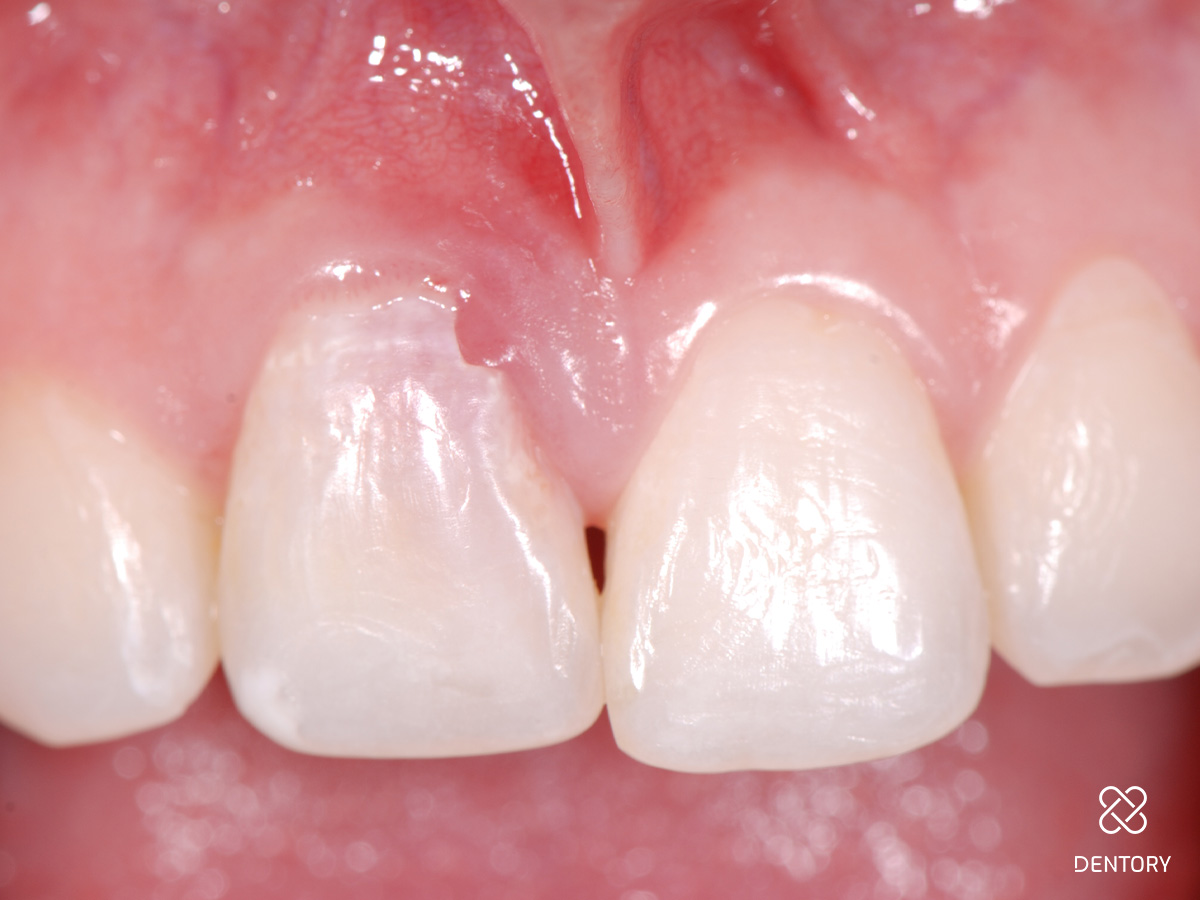

Abbildung 1

Ausgangssituation: Nicht erhaltungswürdiger Zahn 11 aufgrund einer externen Resorption.